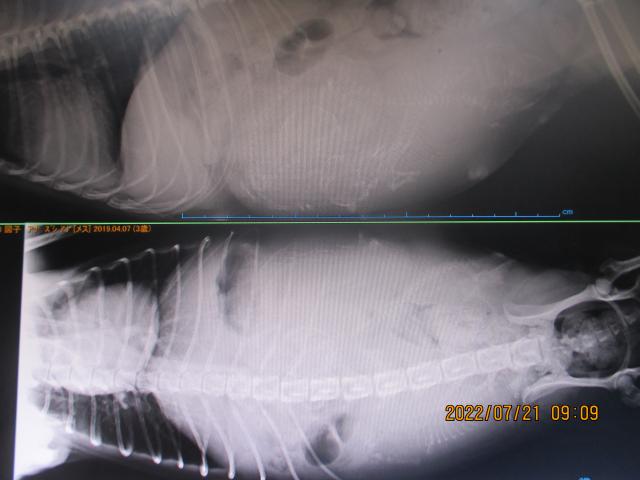

また、このワンちゃんの出生記録を、ご購入の際、プレゼント!!

(パパ・ママ・交配写真・妊娠レントゲン写真・出産前・出産後・成長記録等)